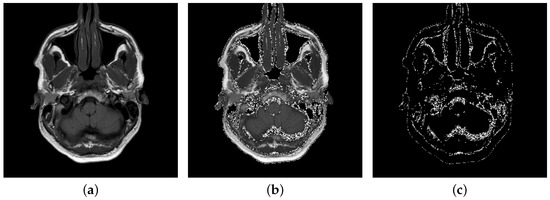

- Specify the input intervals of gray levels of non-black pixels, where a and b determine the boundaries of the container.

- Index the image pixels by consecutive passing through columns and separate those that fall within the interval .

- Convert encrypted data to binary sequence using ASCII table.

- Consecutively embed the encrypted data into the last bits of the pixels from the interval

- The list output pixels is checked to see if their new values are in the input interval. For those pixels that fall outside this range, their value increases by if their new values are below the minimum value of the interval or decreases by if the maximum value of the range is exceeded.